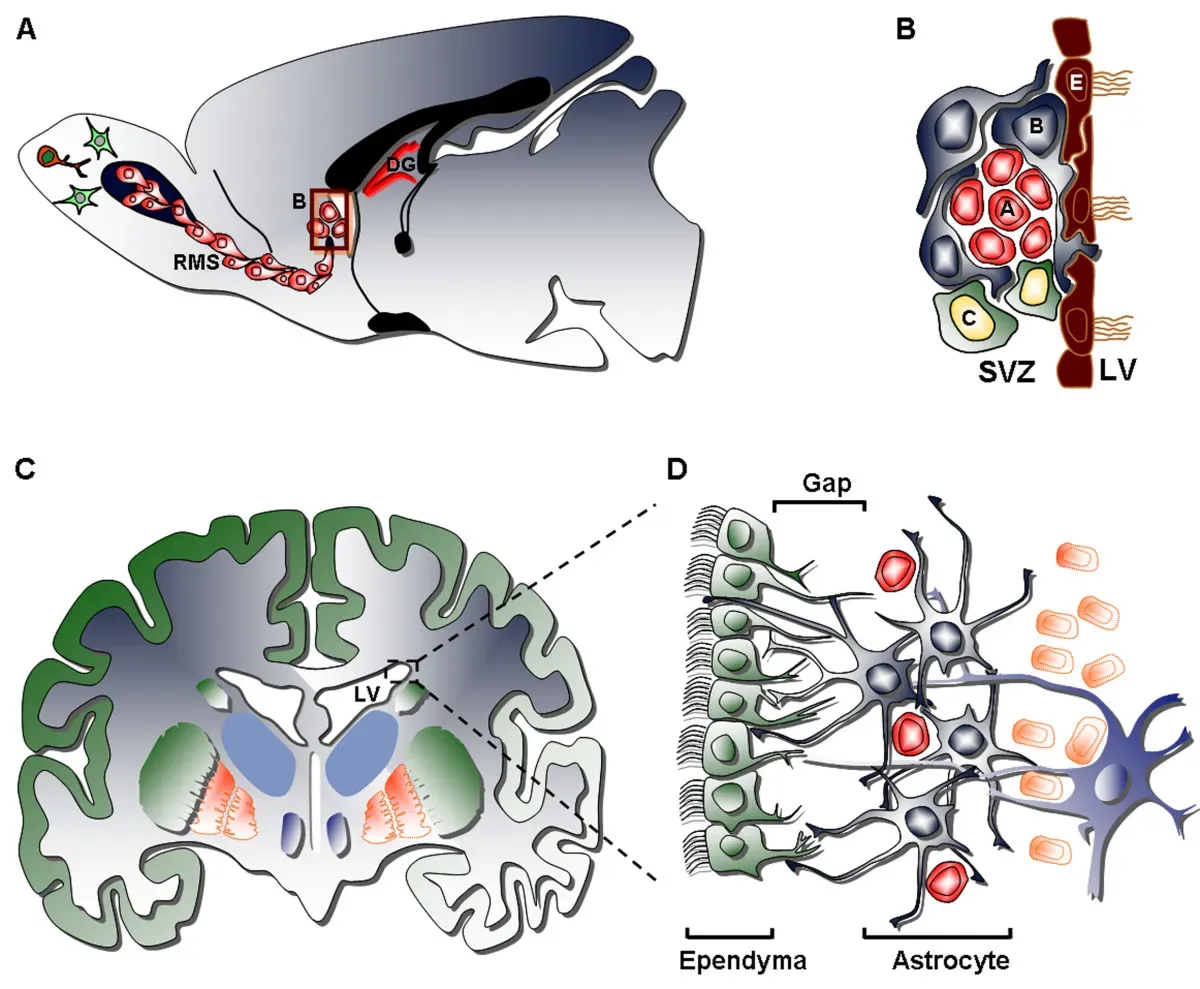

Adults Can Grow Brand New Neurons, and That Changes Everything

For most of the 20th century, neuroscientists held firm to the idea that you were born with all the neurons you’d ever have. Lose them, and they’re gone forever. That idea, it turns out, was wrong. Neuroscientists long believed that you’re born with all the neurons you’ll ever have. Evidence has slowly accumulated to suggest that adults can form new neurons, a process called neurogenesis. Until recently, the evidence was mostly circumstantial and controversial. This year, researchers discovered newly formed neurons and the precursor cells that birthed them in the brains of adults, some as old as age 78.

This is enormously significant. Neurogenesis has spurred an interest in stem cell research, which could lead to an enhancement of neurogenesis in adults who suffer from stroke, Alzheimer’s disease, Parkinson’s disease, or depression. Research suggests that Alzheimer’s disease in particular is associated with a marked decline in neurogenesis. In other words, the discovery isn’t just academically fascinating. It could become the foundation of treatments that genuinely reverse damage to the aging brain.